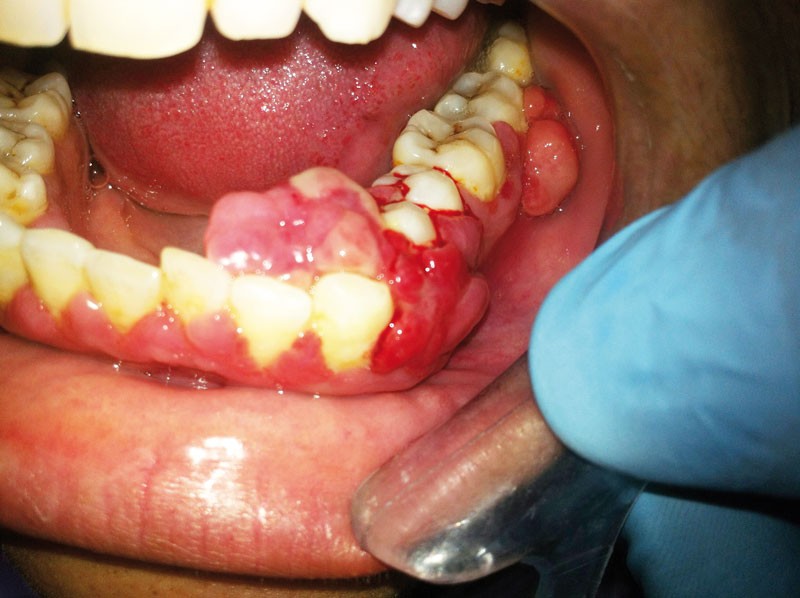

Elles s’identifient par une inflammation gingivale, caractérisée par une gencive rouge, voire violacée, œdématiée, qui saigne au brossage et/ou spontanément (fig. 1).

La spécificité des gingivites est l’absence de perte d’attache (ou de poches parodontales) et de destruction osseuse.